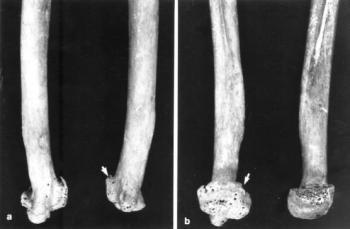

72. ábra. Nemcsak a hosszú csövescsontokon (a kép), hanem a kézközép csontjain (b kép) is arthrosisos, subchondralis osteoscelrosis rtg-tünetei láthatók